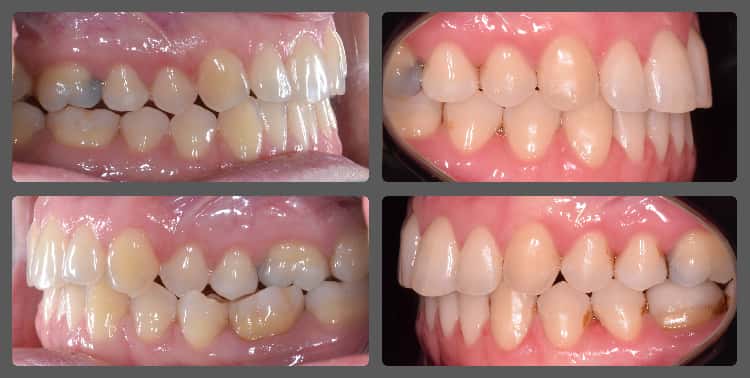

Dorina testvére kezelése után vágott bele a fogszabályozásba. Az előreálló felső metszőfogait, és a növekedésben lemaradt, hátrahelyezett alsó állcsont pozícióját kellett korrigálnunk. A vizsgálat során enyhe felső fogívszűkületet, valamint jelentős disztálharapást diagnosztizáltam. Mivel Dorináék tökéletes időben jelentkeztek, ezért két fázisú kezelés mellett döntöttünk, ahol az első fázisban egy Twin-block nevű kivehető funkcionális fogszabályozó készülékkel helyes pozícióba helyeztük az alsó állcsontot és elkezdtük a felső metszőfogak tengelyállásának korrekcióját. A második fázisban hagyományos rögzített fogszabályzó, extraradikuláris fogszabályozási miniimplantátumok és intermaxilláris gumihúzás segítségével egy igazán szép végeredményt értünk el. Az első fázis 1.5 éven át tartott, a csontnövekedés befejeztéig, majd a második fázis 20 hónap után ért véget. Dorina végig nagyon együttműködő volt, ennek is köszönhető a közel tökéletes eredményünk! Jól látható, hogy a megfelelő kezelési terv felállítását követően hagyományos módszerekkel is gyönyörű mosoly varázsolható a pácienseink arcára.